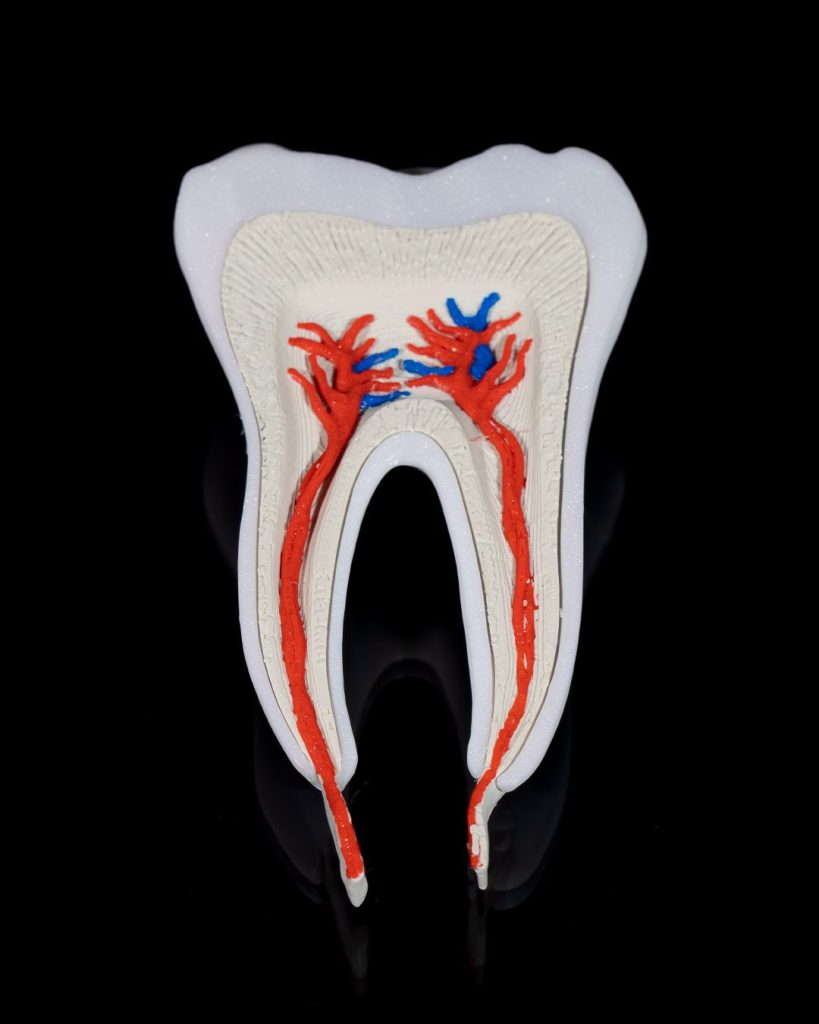

Human Tooth Anatomical Model

Example Short Description.

- Articulated and flexible for fun and display

- Intricately detailed to use

- Perfect as decor, a desk companion, or a thoughtful gift